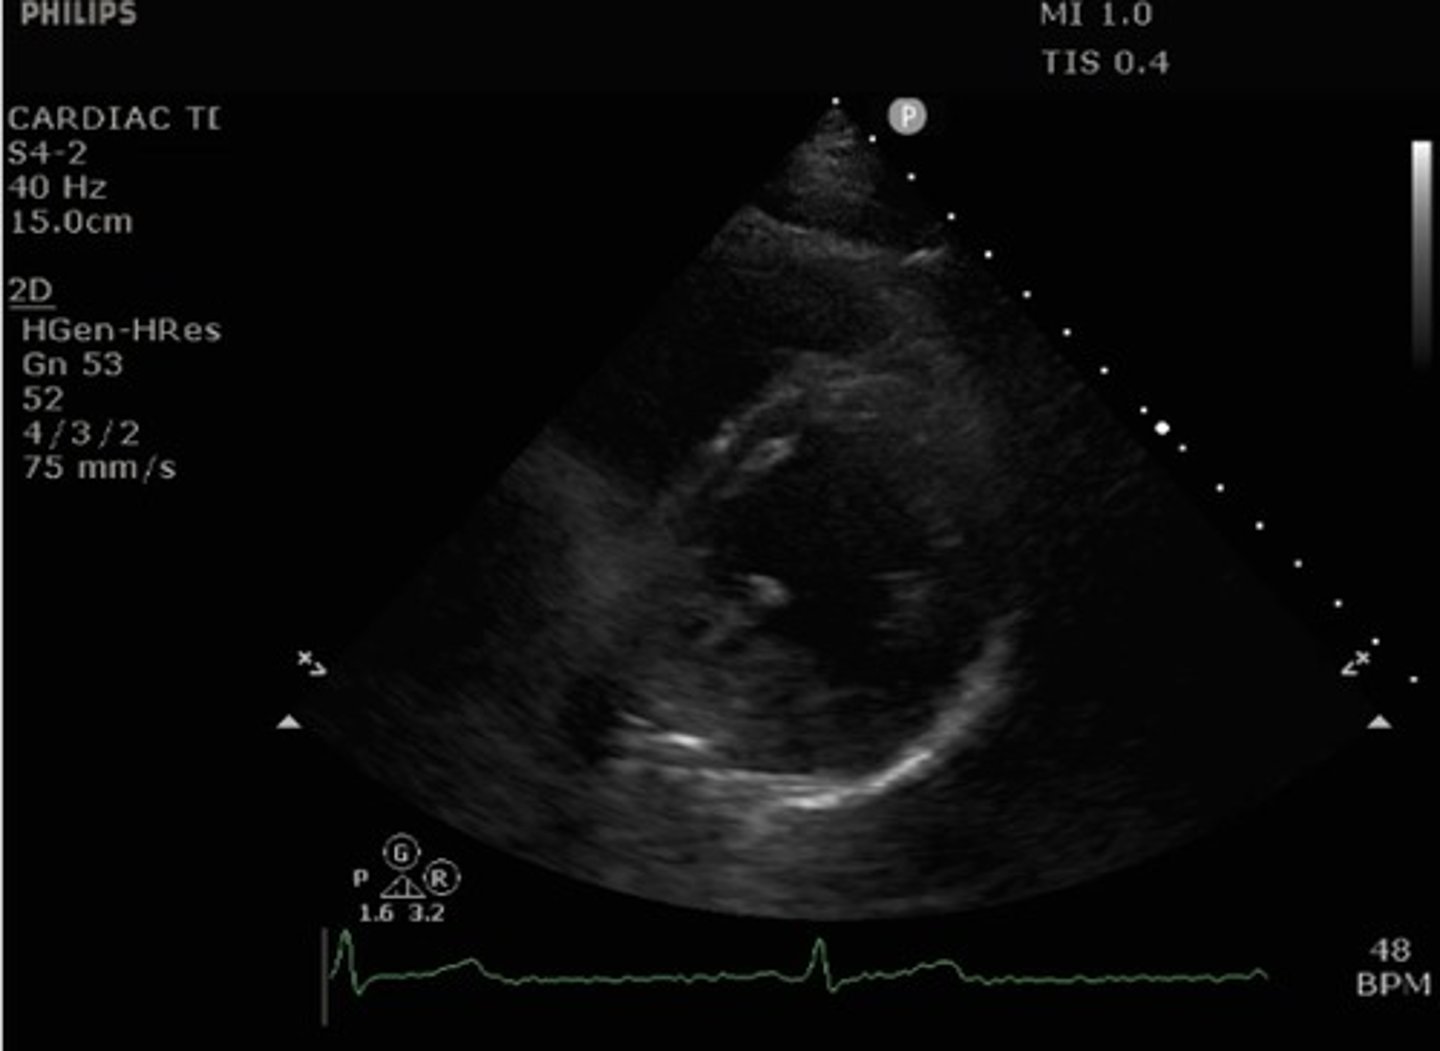

Parasternal short axis mid-ventricle

What view of the heart is this?

what structures are seen with parasternal short axis mid-ventricular view?